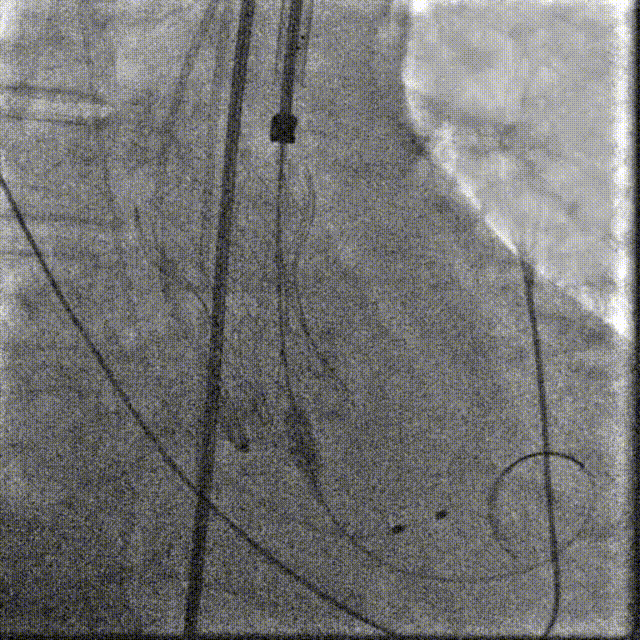

TaurusElite AV26瓣膜轻松过弓跨瓣,瓣膜初始定位瓣环0位,120bpm起搏下精准释放,释放到工作位后造影显示锚定充足,位置良好,冠脉未见遮挡,继续完成释放。

瓣膜初始定位

瓣膜释放过程